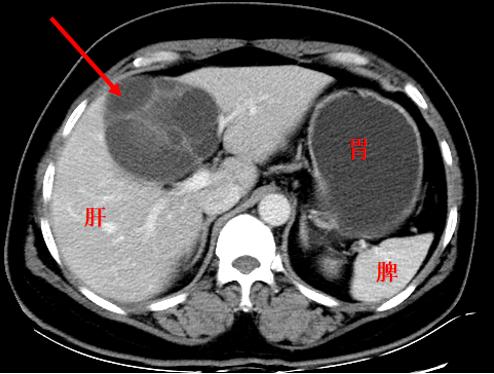

肝囊肿,并不是肿瘤

举一些实例来看:囊肿、血肿、肉芽组织增殖等,都不是肿瘤,但却通常表现为肿块,在前面的病例中,小李的腕部所摸到的腱鞘囊肿,就表现为肿块,但却并不是肿瘤(有时也被称为肿瘤样病变)。

与前图相似,但却是真肿瘤(囊腺瘤)